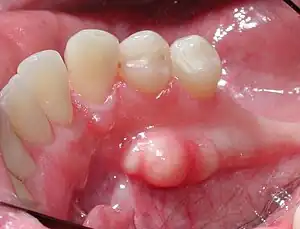

| Mandibular torus in premolar area | |

Torus mandibularis is a bony growth in the mandible along the surface nearest to the tongue.[1] Mandibular tori usually are present near the premolars and above the location on the mandible of the mylohyoid muscle attachment.[2] In 90% of cases, a torus is on both inner sides of the mandible (left and right); however, they may differ in size.